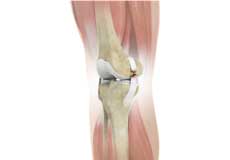

Muscles of the Knee

There are two major muscles in the knee - the quadriceps and the hamstrings, which enable movement of the knee joint. The quadriceps muscles are located in front of the thigh. When the quadriceps muscles contract, the knee straightens. The hamstrings are located at the back of the thigh. When the hamstring muscles contract, the knee bends.

Tendons of the Knee

A tendon is a tissue that attaches a muscle to a bone. The quadriceps muscles of the knee meet just above the patella and attach to it through a tendon called the quadriceps tendon. The patella further attaches to the tibia through a tendon called the patella tendon. The quadriceps muscle, quadriceps tendon, and patellar tendon all work together to straighten the knee. Similarly, the hamstring muscles at the back of the leg are attached to the knee joint with the hamstring tendon.